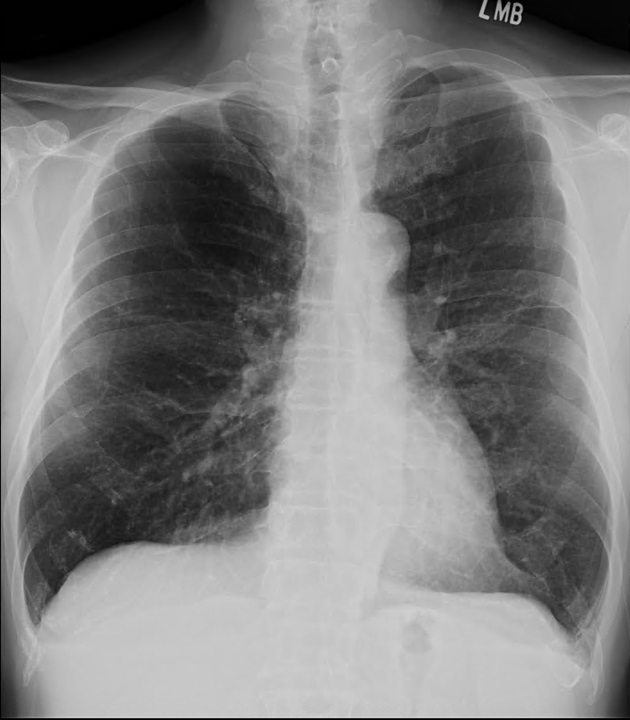

A 64-year-old male with chest pain and tightness during exertion for 2 months, relieved by rest. Past history: type 2 diabetes, hypertension. No smoking or family history. Sinus rhythm EKG. Clear lungs, no cardiomegaly on chest x-ray. Angiography: LM bifurcation (Medina 1,1,1), diffuse LAD, severe LCX AS, 95% eccentric LAD, long RCA CTO. Syntax score 25, EuroScore II 0.84%. CABG advised, patient sought second opinion here.